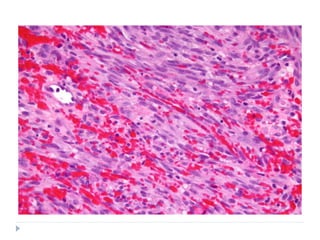

HISTOPATHOLOGY

 They vary in histologic grade

 WELL DIFFERENTIATED

 Multiple plump fibroblasts with pale eosinophilic cytoplasm and

deeply stained spindled nuclei

 Malignant cells are dispersed in rich collagen background

 Histologically normal mitotic figures are seen in few numbers

 Cells and nuclei are not pleomorphic

 INTERMEDIATE GRADE

 Cellular

 Have HERRING BONE PATTERN: parallel sheets of cell

arranged in intertwining whorls

 Slight degree of cellular pleomorphism

 Moderate amount of mature collagen

 HIGH GRADE

 Very cellular with marked cellular atypia

 Marked mitotic activity

 Sparse matrix

 Multinucleated giant cells may be seen

 NO MALIGNANT OSTEOID FORMATION SHOULD BE

SEEN

 Extremely anaplastic and pleomorphic cells with bizzare

nuclei